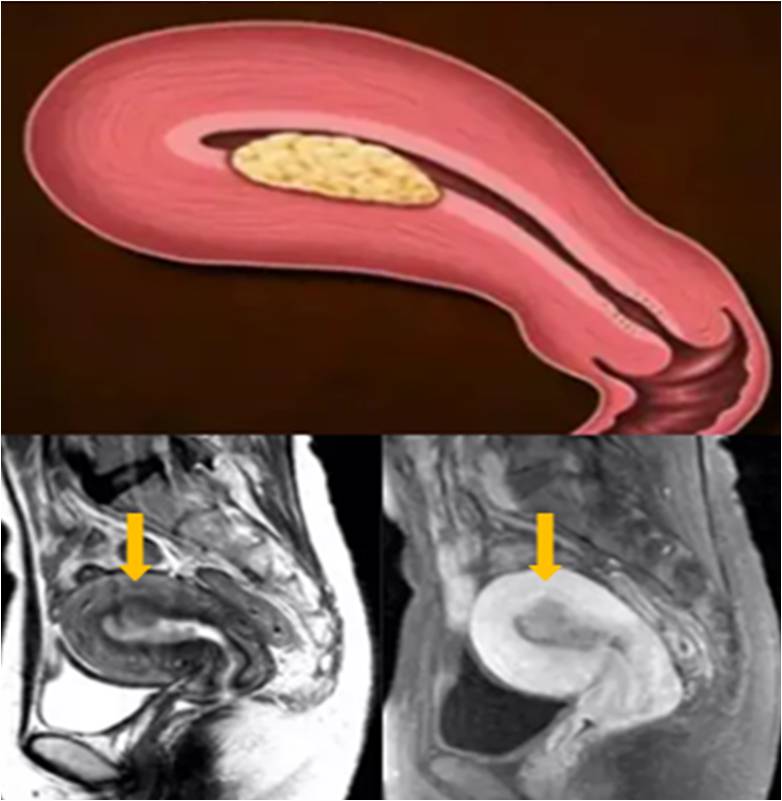

1. 子宮體四層結構(T2WI):

子宮內膜-高信號

結合帶-低信號

子宮肌層-中等信號

漿膜層-低信號

1. 子宮腔增大,腫物呈息肉樣或彌漫性生長;

2. T2WI:低信號結合帶是否完整,是判斷肌層有無受累的重要標志;

3. 動態增強掃描:內膜癌增強弱于肌層,尤其在動脈期;內膜下強化帶是否完整。